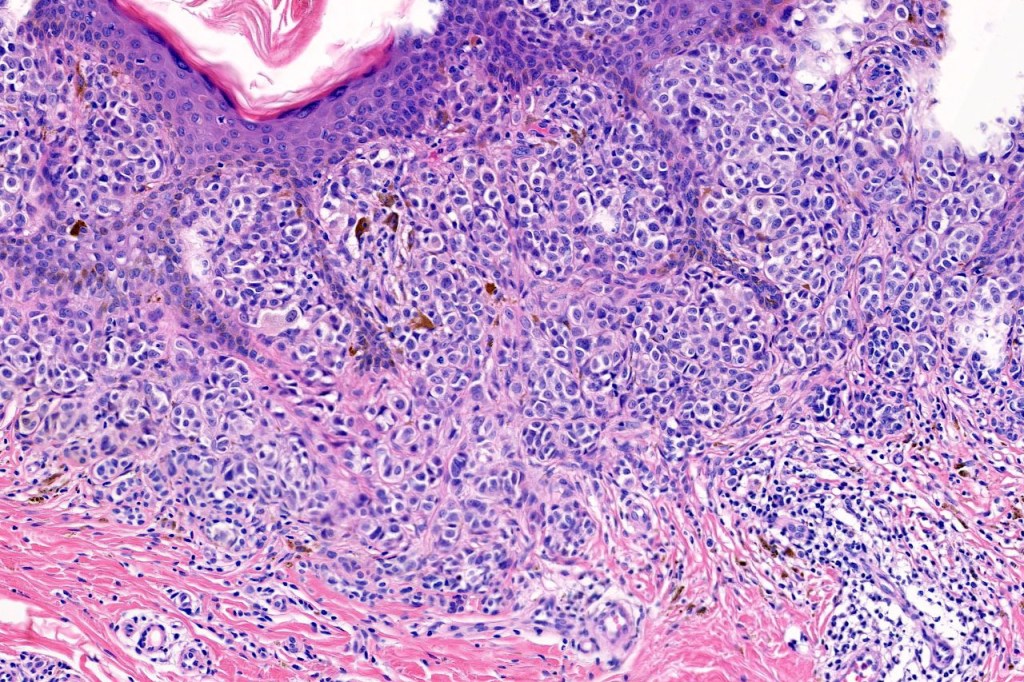

•Verrucous or dome-shaped, at low power, the lesion looks like a nevus

•Minimal or no junctional component

•Expansile nodules or diffuse

•Compression of connective tissue

•Stretched & elongated rete ridges in verrucous variants

•Subtle or not so subtle impaired maturation with depth (sometimes this is evident at scanning magnification)

•Subtle nucleolar prominence

•Subtle pleomorphism

•Mitoses invariable including often in the deep aspect